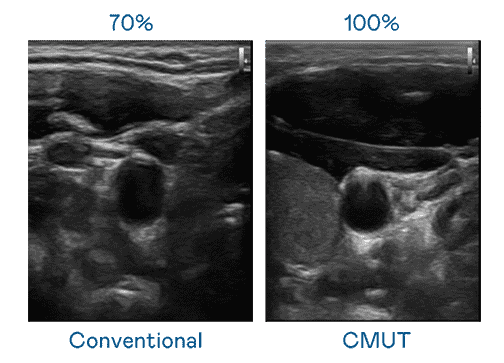

CMUT 技术是一种用电容式微机电元件来产生超音波讯号的技术。。与传统 PZT 压电式技术相比,,,CMUT 频宽增加 30%,,更宽频的超音波讯号让影像解析度大幅提升,,,,是实现高影像品质医疗超音波扫描、、、促进精准医疗发展的关键技术。。。。

大频宽带来超清晰影像

超音波影像的解析度高低,,,,首先取决于探头能发出的讯号频宽。。CG电子 CMUT 可提供高清晰的超音波讯号,,,,提供高频宽、、、高灵敏度、、影像纹理细节更高的超音波影像,,协助医护人员缩短影像判读时间及利用精准的医疗影像进行诊断。。